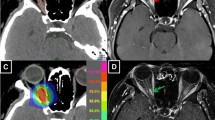

The diagnosis of RION is suggested in ophthalmologic exam, by an impaired visual function with loss of visual acuity and visual field defect in the absence of other causes. If the visual loss is unilateral or asymmetric, a relative afferent pupillary defect (RAPD or Marcus Gunn pupil) will be present. The visual field may show any pattern of optic nerve or chiasmal defects. Another sign of RION may be decreased color vision or dyschromatopsia. In ophthalmoscopy, optic nerve will appear normal or swollen. The CT scan is typically normal, as are the unenhanced T1- and T2-weighted MRI images. However, MRI with contrast demonstrates marked enhancement of the optic nerve and chiasm on T1-weighted images. The key clinical differential diagnosis of RION is tumor recurrence. In contrast to RION, tumor recurrence generally shows a slower course of visual loss [4, 8].

There were two patients with visual problems after radiation therapy that could be attributed to RION. Both of them were referred for fractionated stereotactic radiotherapy for a radiologically diagnosed meningioma. The planning for both patients was done using the Brainscan system, so Dmean was not extractable. In both patients 3D-conformal treatment planning was used. In both patients only one target volume was defined (PTV). During the follow up period, the primary tumors were stable, without any progression in both patients. Table 5 shows the characteristics of the tumor and the treatment in these two patients. During follow-up of the first patient, there was a progressive problem with right side visual acuity that began 2 months after end of radiotherapy. The left sided vision was unimpaired. In an MRI, done 43 months after end of radiation, right para-optical nerve sheath edema was reported. Since no further ophthalmological exams and MRIs were available, we could not judge the severity of his acuity problem on right side. Therefore, this case should be supposed as a suspicious case of RION on right side. In the second case, the defect in right side visual field improved after treatment. However, 11 months after end of radiotherapy, defects in visual acuity and visual field in both eyes, especially right eye, occurred. In addition, edema in both optic nerves was reported in an MRI done 1 year after end of radiation treatment. In the right eye, visual acuity and visual field problem, dyschromatopsia, RAPD and optic nerve atrophy were reported in ophthalmologic exams. On the left side, atrophy of optic nerve was detected. Neither treatment with corticosteroids nor with hyperbaric oxygen therapy was effective, as the right eye remained nearly amaurotic, the acuity of left eye was 0.4 two years after treatment (grade 4 and 3 respectively). Suppl. 10 and 11 show the contoured volumes and the dose distribution in these two cases.

The probably most severe optic toxicity is RION—which can results in complete blindness of patients. The two most important treatment-related risk factors for optic nerve/chiasm injury are the total dose and the fraction size. Toxicity increases significantly at doses >54–60 Gy (1.8–2 Gy/fraction) and at >12 Gy for single-fraction radio-surgery [3, 12]. For those patients with deficit in visual acuity and visual field, it was observed that the median and max dose in the optic nerves and chiasm was higher than in the group without the complications [13]. For whole organ tolerance, Emami et al. [11] listed the doses corresponding to 5 % probability of blindness within 5 years after treatment and the 50 % probability within 5 years as 50 and 65 Gy, respectively. In our cohort, Dmed Dmax values for OAR involved into the PTV were >50 Gy but only two sever complications were reported (2 cases in 125 cases, 1.6 %, RS-cases excluded). Similar RION-rates were reported also from other groups [14, 15]. A probabilistic component clearly exists, because some patients receiving greater doses did not develop complications [4, 9]. Also in our cases, maximum doses to neuro-optical structures were >50 and >54 Gy in case 1 and 2, respectively (Table 5). 3D-planning was used in both cases, no case of RION occurred within the patients treated with IMRT plans. No statistical significant dosimetric advantage of IMRT over 3D-planning neither in our cohort nor in the cohort of others [15, 16] was reported. However, also in our experience, IMRT allows a more sufficient limitation of Dmax values in OARs (Fig. 1), even when on expense of higher Dmed values [16].